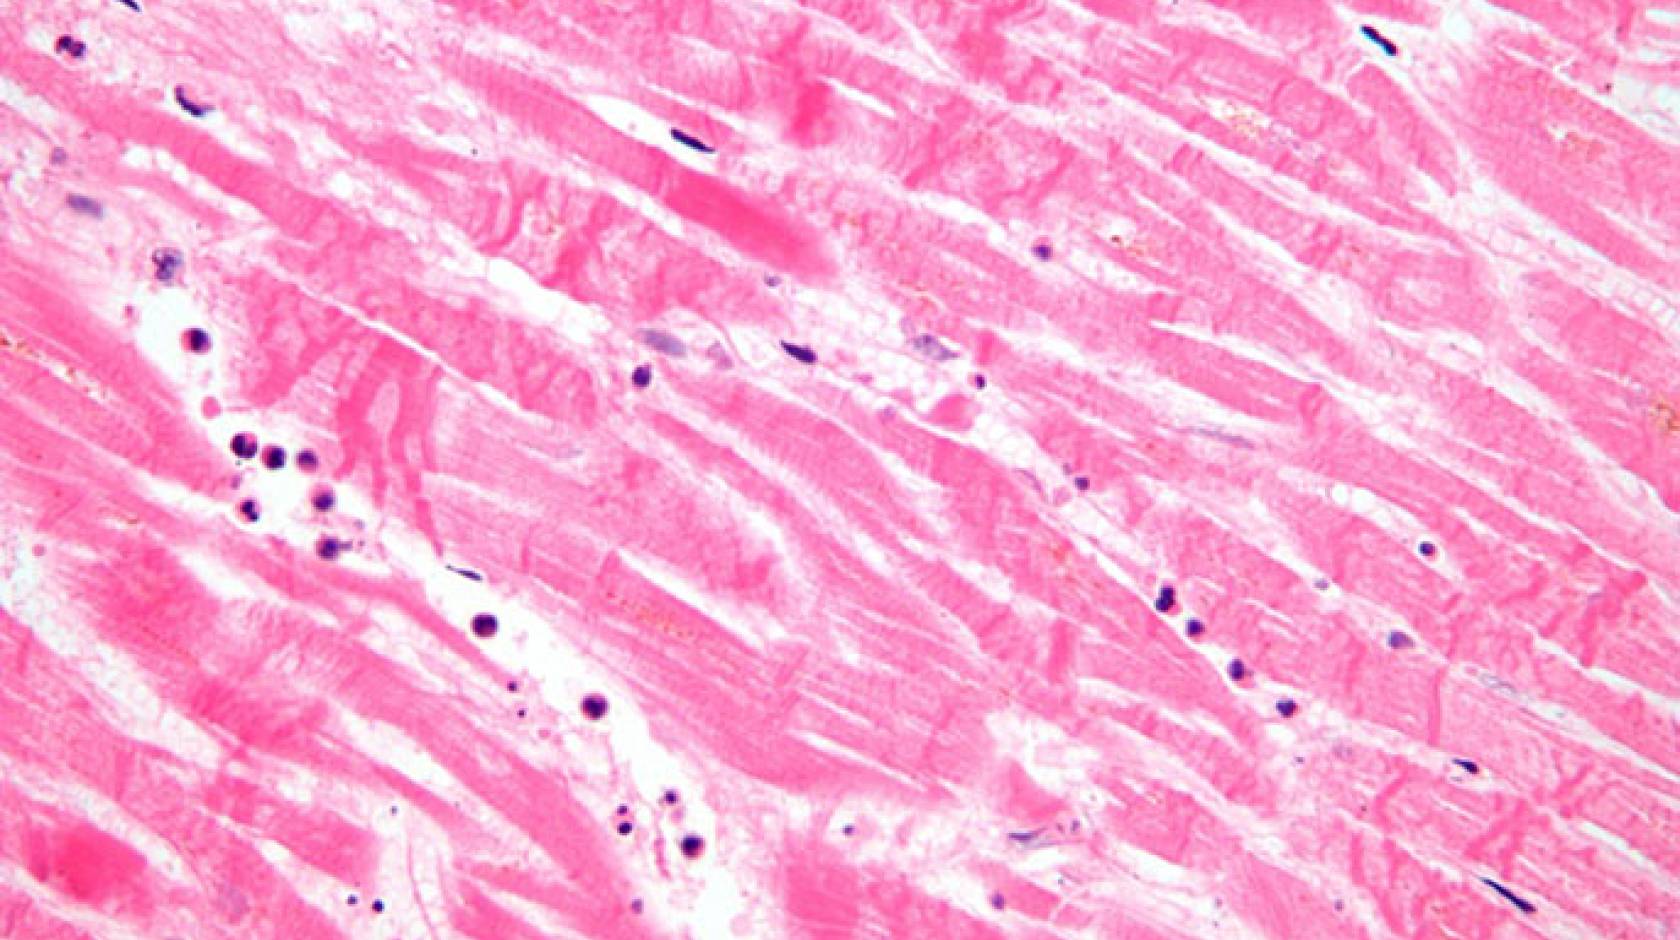

Credit: Ashley Fong, CC BY-ND

I also discovered that the most maturation occurs when the cells are grown in a 3D scaffold, rather than a 2D scaffold in a traditional flat petri dish. This finding supports the idea that placing the cells in an environment more like their natural habitat can instruct them to develop and mature. We still don’t know how the scaffold actually issues its instructions to the cardiomyocytes to mature, but for now we’re glad it seems to work.